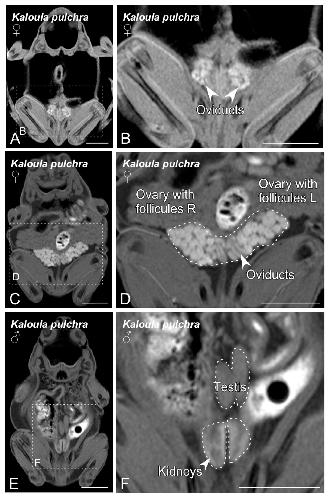

Figure 2. Magnetic resonance imaging (MRI) slices selected to classify Kaloula pulchra anurans by sex. Images from (A) to (D) show the main sexual structures identified in a non-gravid (A,B) and gravid (C,D) Kaloula pulchra female. Images (E) and (F) show testis and kidneys in a Kaloula pulchra male. The dashed lines in (A,C,E) indicate the magnification photos showed in (B,D,F). Scale bars = 1 cm.